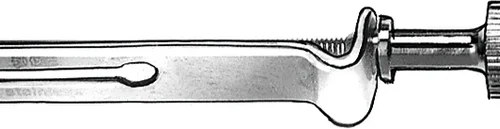

Markert kurvatur for optimal gjenoppretting av tannanatomien. NiTin matrisebånd er optimalt forkonturert og 0,038mm tynne. De består av polert, bleitoten rustfritt stål. De er tilgjengelige i fem forskjellige størrelser. Deres ideelle form hjelper deg med å gjenopprette tannanatomien fullstendig.